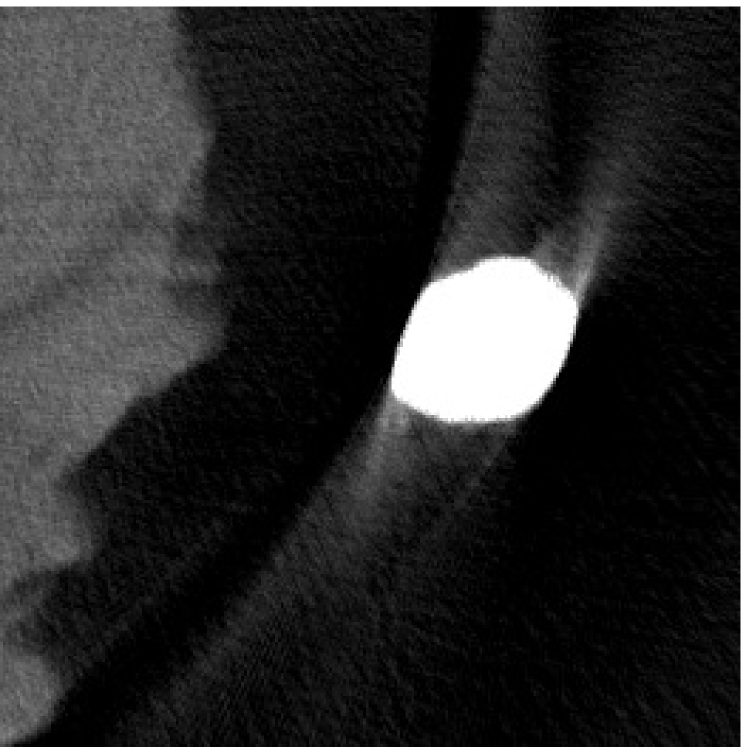

4.2 Numerical experiments: real data

We perform a CT scan of a chicken leg placed in a disposable cup (Figure 10(a)). We first scan the chicken leg without metals (Figure 10(b)) to create a reference image using FBP algorithm. Then, we place two steel thread nails on each side of the chicken leg and scan the subject again using the same scanning protocol (Figure 10(c)). The projection data is acquired from a MicroCT scanner equipped at the Division of Nuclear Technology and Applications, Institute of High Energy Physics, Chinese Academy of Sciences. The X-ray source is with 90 kV and 70 mA energy and the flat plane detector contains pixels. The scanning trajectory is a full circle with equally spaced views at per view. The physical size of each detector unit is . The distance from the X-ray source to the detector is . In order to conduct a 2D experiment, we choose the 512th row of the detector array.

Figure 11 shows the images reconstructed using FBP, the analysis model (2.12), the inpainting model (2.13) and the segmented image from the image obtained by (2.14). The reference image without metal implants are shown in Figure 11(a). All the images in this subsection are displayed within the grayscale interval . The segmented image shown in Figure 11(e) is used to estimate the weights needed in NMAR and the re-weighted JSR model.

Figure 12 shows a comparison between the reconstructed image from NMAR and the unweighted JSR model. Figure 13 shows a comparison between the reconstructed images from TV-FADM and the proposed re-weighted JSR model. Zoom-in views are provided in both Figure 12 and Figure 13 for a better visual assessment. As one can see that the reconstructed images from the unweighted JSR model and TV-FADM are less noisy than NMAR as indicated by the blue ellipse curve, whereas NMAR does a better job in preserving image features and suppressing metal artifacts. However, there are also new artifacts around the metal on the right as shown in Figure 12(d). The proposed re-weighted JSR model has best overall performance in terms of feature preservation, noise and metal artifact reduction.